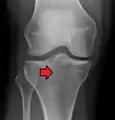

A tibial plateau fracture seen on X-ray